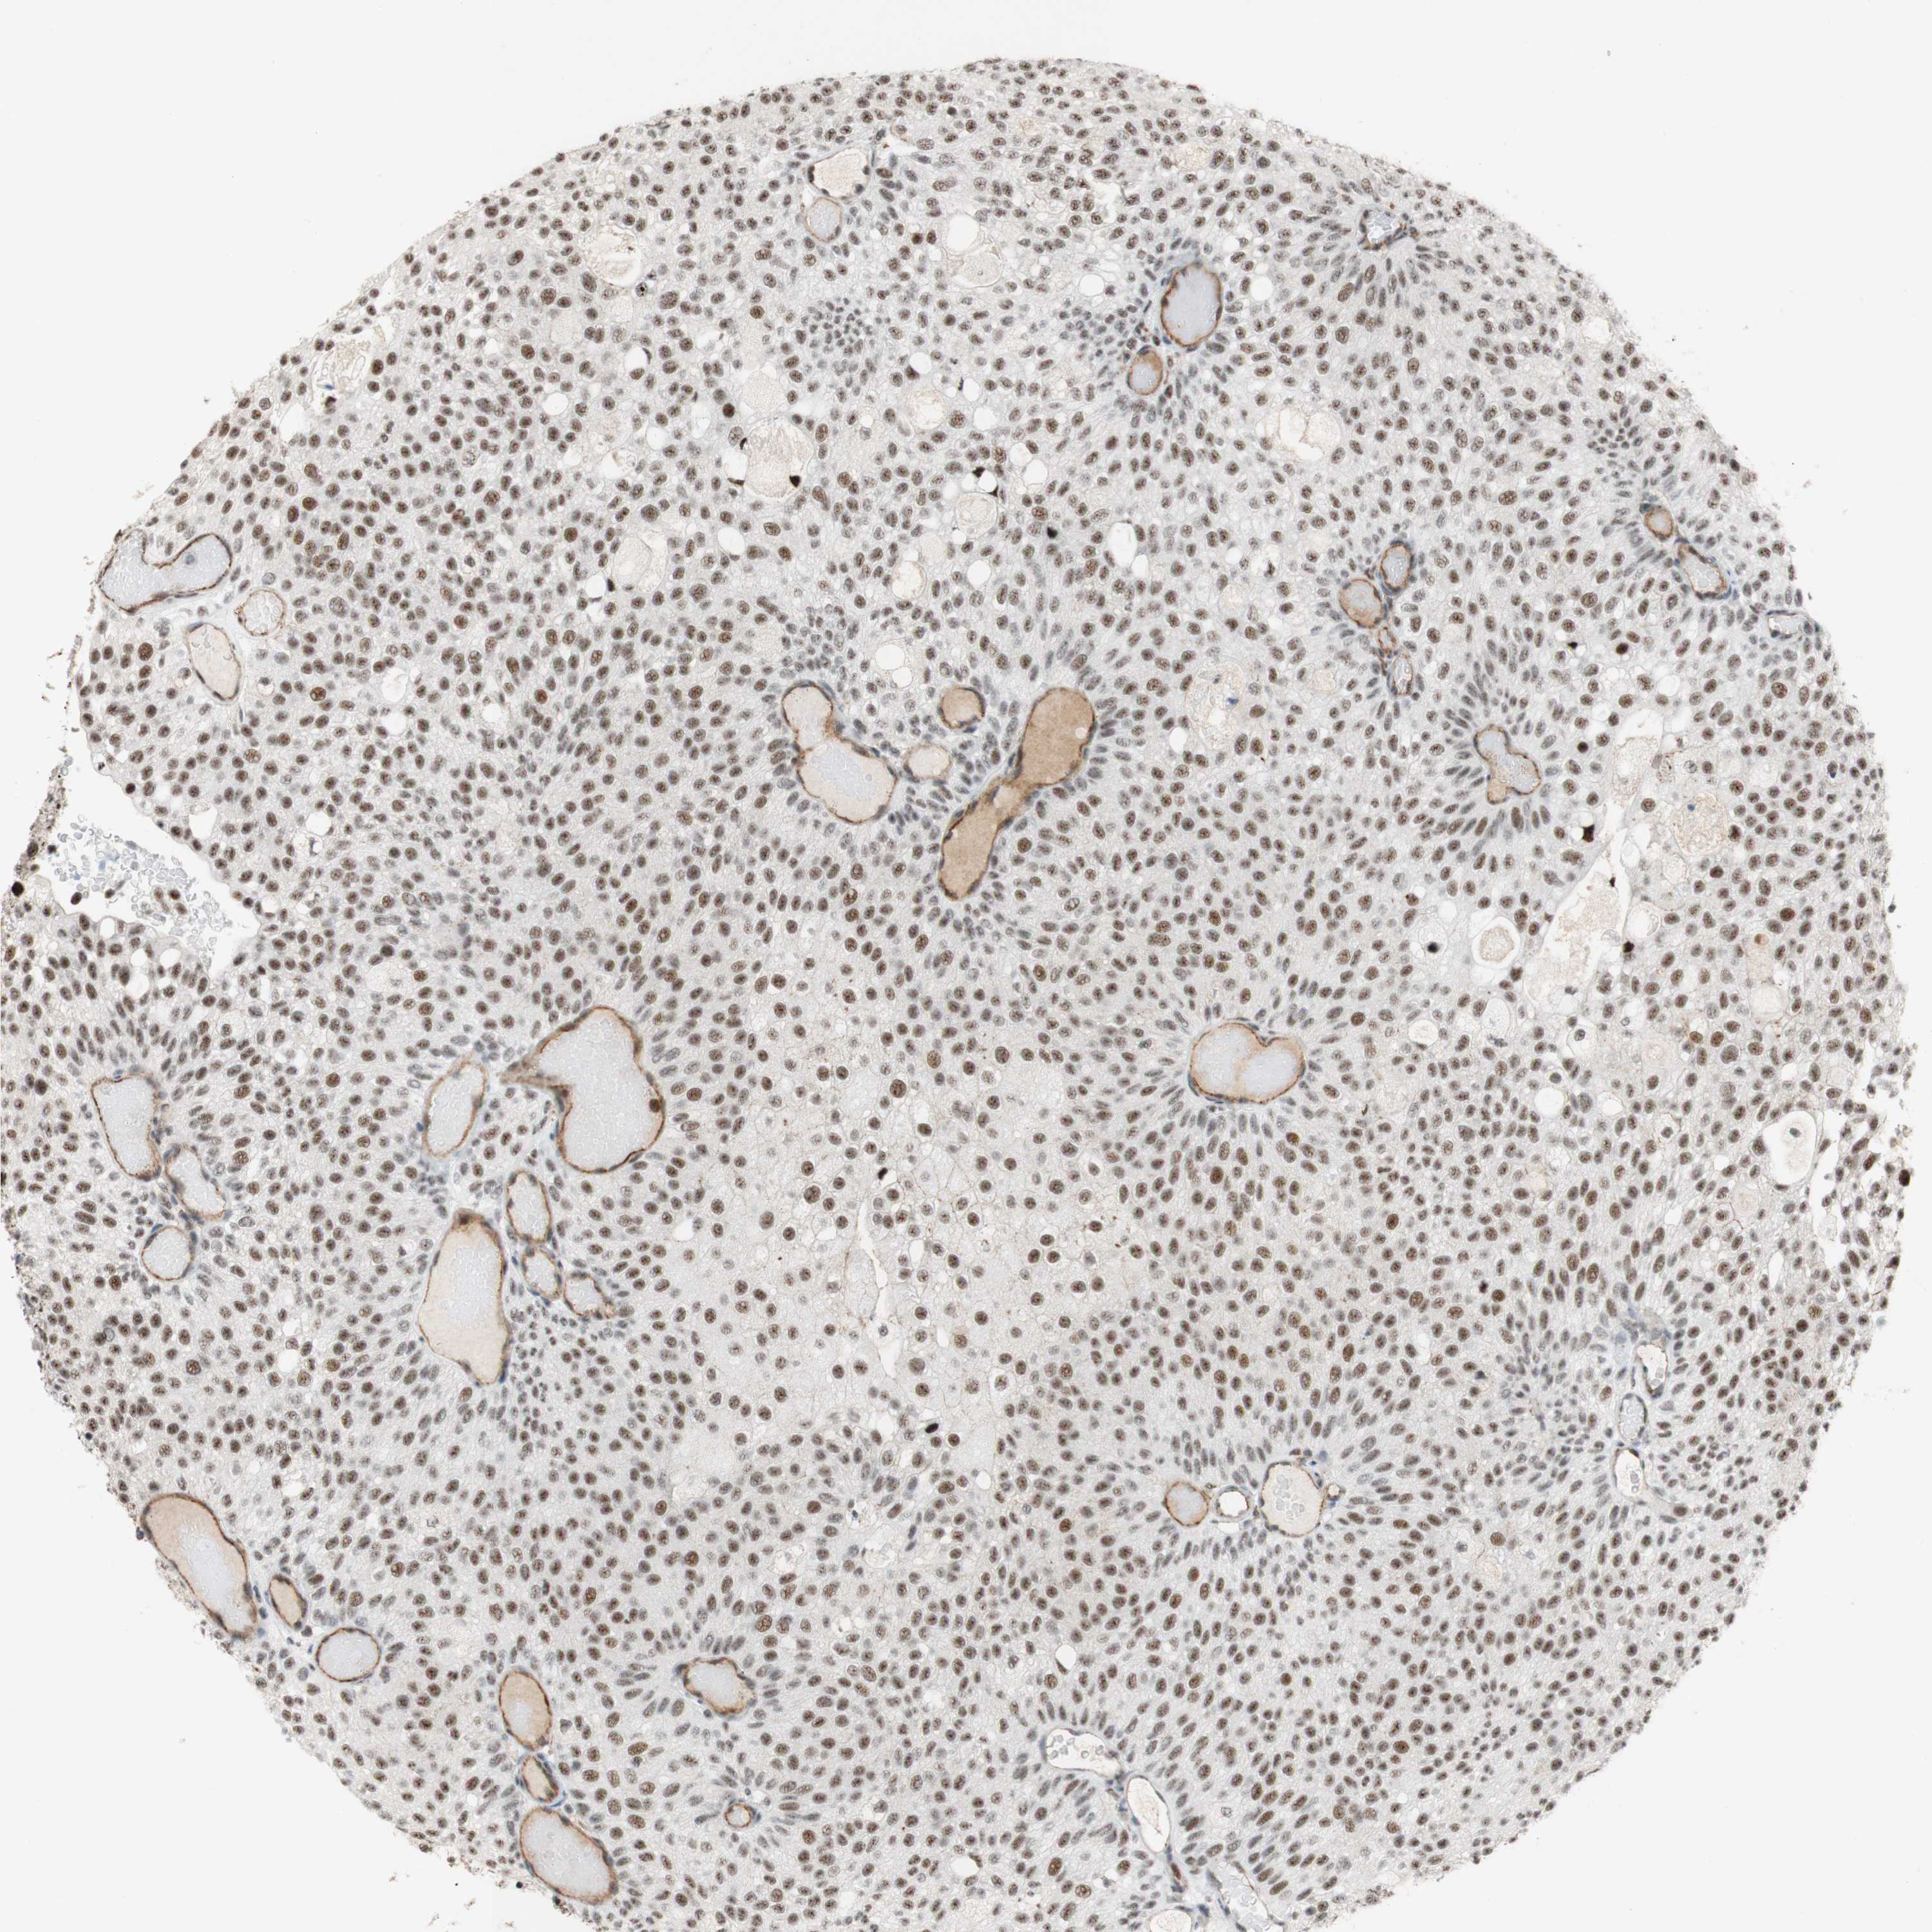

UROTHELIAL CANCER - Protein expressioni

A mouse-over function shows sample information and annotation data. Click on an image to view it in a full screen mode. Samples can be filtered based on level of antibody staining by selecting one or several of the following categories: high, medium, low and not detected. The assay and annotation is described here.

Note that samples used for immunohistochemistry by the Human Protein Atlas do not correspond to samples in the TCGA dataset.

Antibody stainingi

Antibody staining in the annotated cell types in the current human tissue is reported as not detected, low, medium, or high, based on conventional immunohistochemistry profiling in selected tissues. This score is based on the combination of the staining intensity and fraction of stained cells.

Each image is clickable and will lead to virtual microscopy that enables deeper exploration of all samples and also displays staining intensity scores, fraction scores and subcellular localization as well as patient and tissue information for each sample.

Antibody HPA011352

Antibody CAB012273

Staining

High

Medium

Low

Not detected

Intensity

Strong

Moderate

Weak

Negative

Quantity

>75%

75%-25%

<25%

None

Location

Nuclear

Cytoplasmic/membranous

Cytoplasmic/membranous,nuclear

Urothelial carcinoma, Low grade

Urothelial carcinoma, High grade